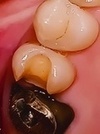

「右下の奥歯が冷たいものでしみる」とご相談いただいた患者様。拝見したところ、古い詰め物(コンポジットレジン)の下ではなく、隣の歯と接する面に小さな虫歯ができていました。

このタイプの虫歯は、進行すると歯の内部に感染が広がり、最終的には神経にまで達するリスクがあります。さらに、隣接面という場所柄、隣の健康な歯まで虫歯にしてしまう可能性もあるため、早急な治療が必要だと診断しました。

治療前(Before)

治療後(After)

拝見したところ、左上の奥歯(第2小臼歯/5番)には、隣の歯と接触する部分に虫歯ができていました。

このまま虫歯を放置すると歯の内部が虫歯菌に感染し、痛みが生じたり神経が死んでしまったりする可能性があります。さらに隣の歯も虫歯になるおそれがあるため、早急に虫歯部分を除去する必要があると診断しました。

周りの歯になじんだ自然な仕上がりで、噛み合わせも問題ありません。